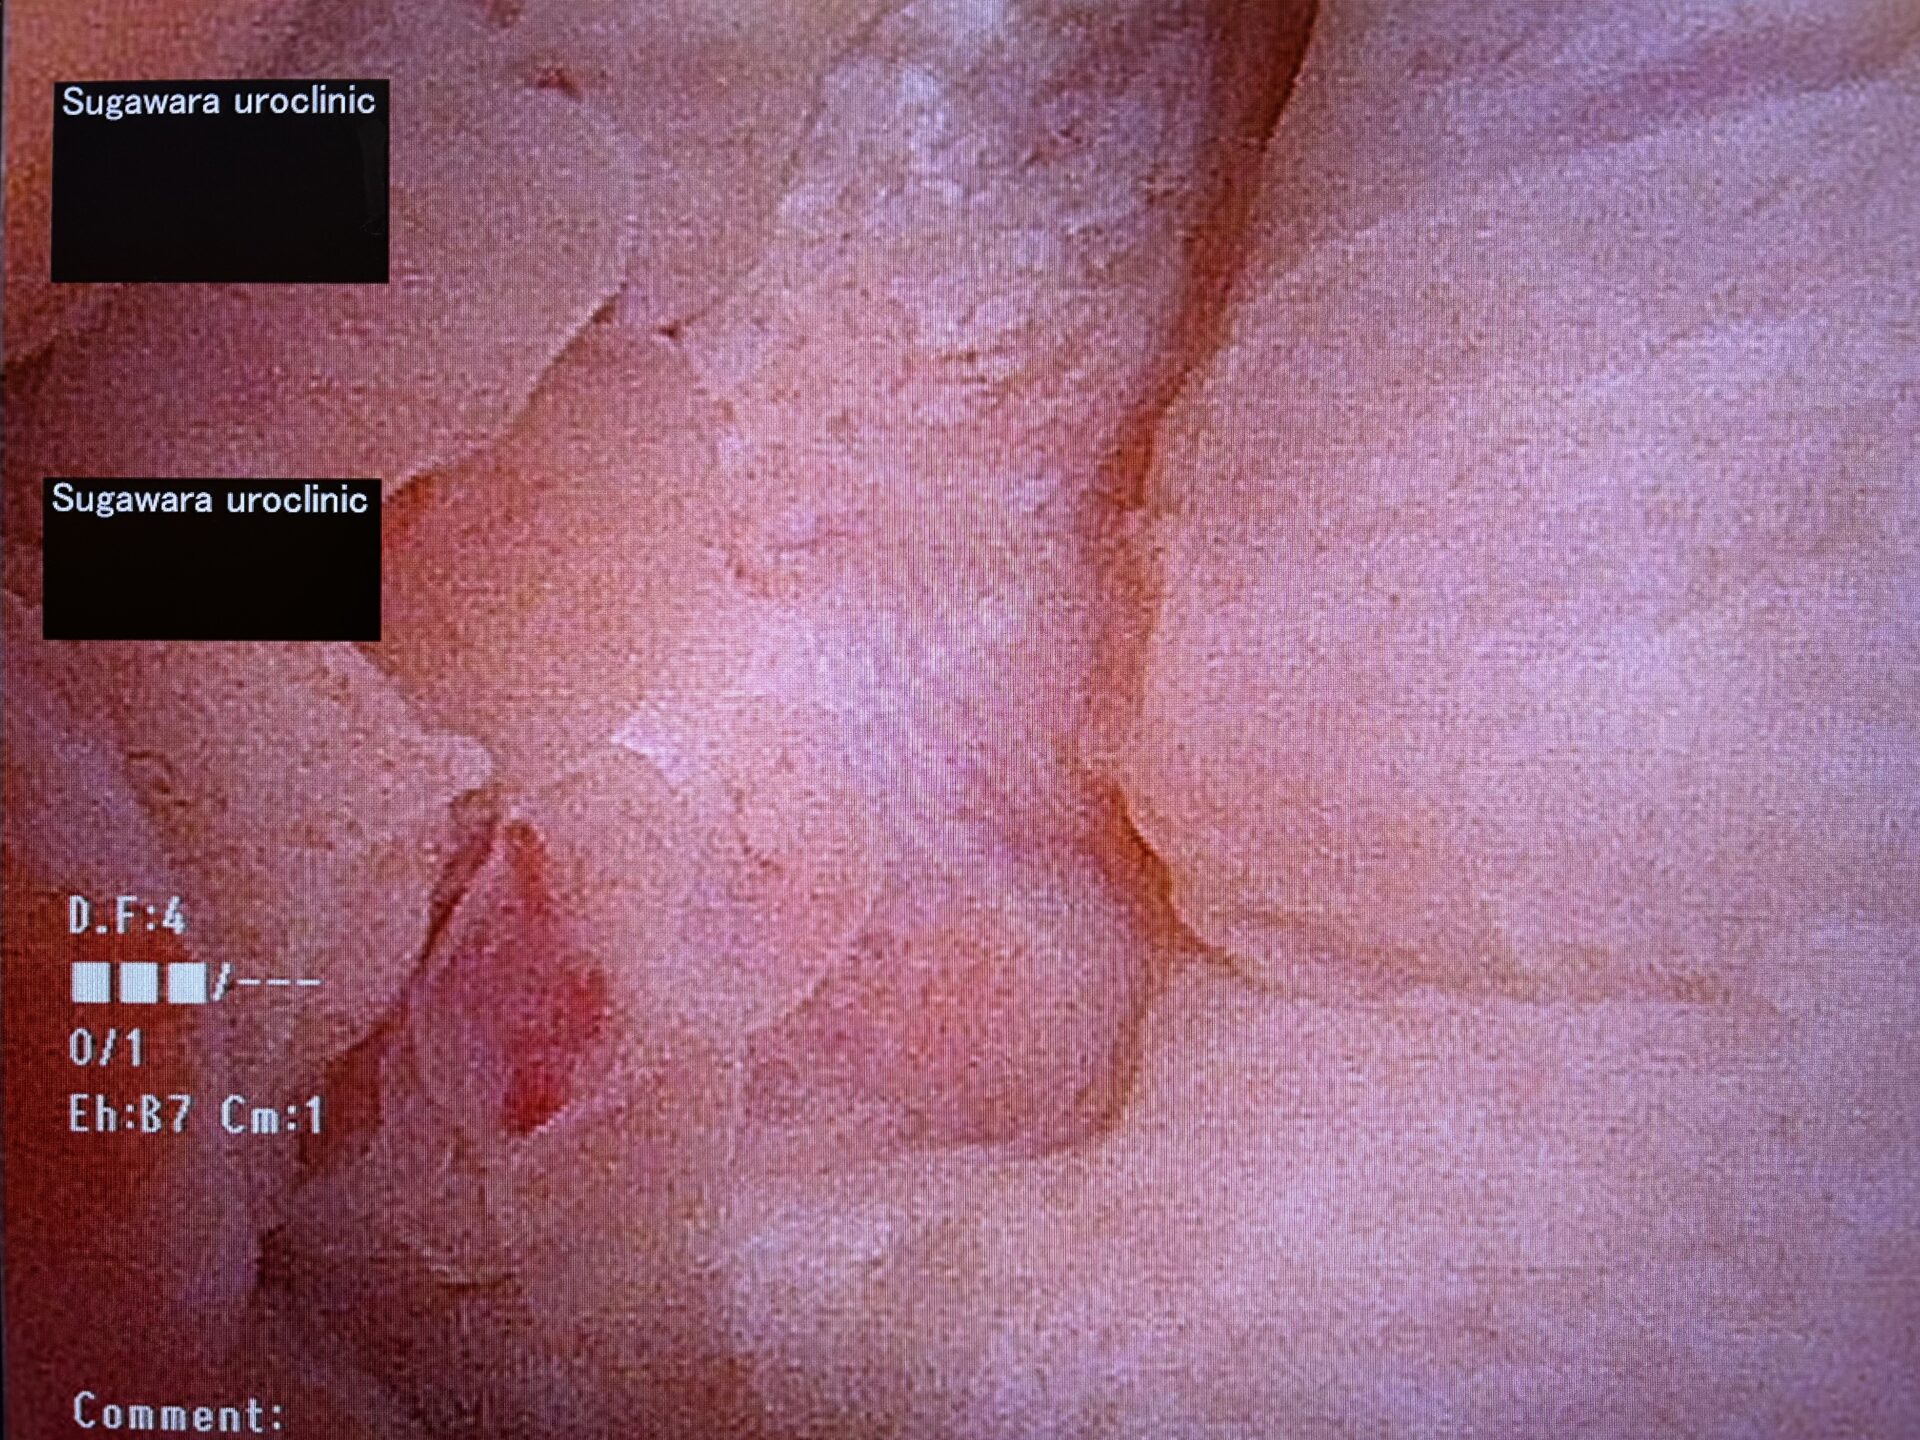

念のために尿路由来ではない事を証明するために膀胱鏡と尿細胞診も検査することとしました。結果は尿細胞診classⅡ(陰性)、膀胱鏡所見でも右尿管口は確認出来るも膀胱粘膜が浮腫状に肥厚しており、一部膀胱壁外から直接浸潤していると考えられる腫瘍性病変も認められました。明らかに膀胱癌などの尿路上皮癌に特徴的な乳頭状腫瘍とは異なる内視鏡所見でした。また、患者さんは約9年前に子宮体癌の広汎子宮全摘術を行っており、CT上認められた手術痕および周囲の腫瘤形成から子宮体癌の局所再発による尿管浸潤または圧排による右水腎症と診断し、かかりつけ婦人科に紹介させて頂きました。

【膀胱鏡所見:膀胱右側壁の肥厚像および膀胱壁外からの腫瘍浸潤】